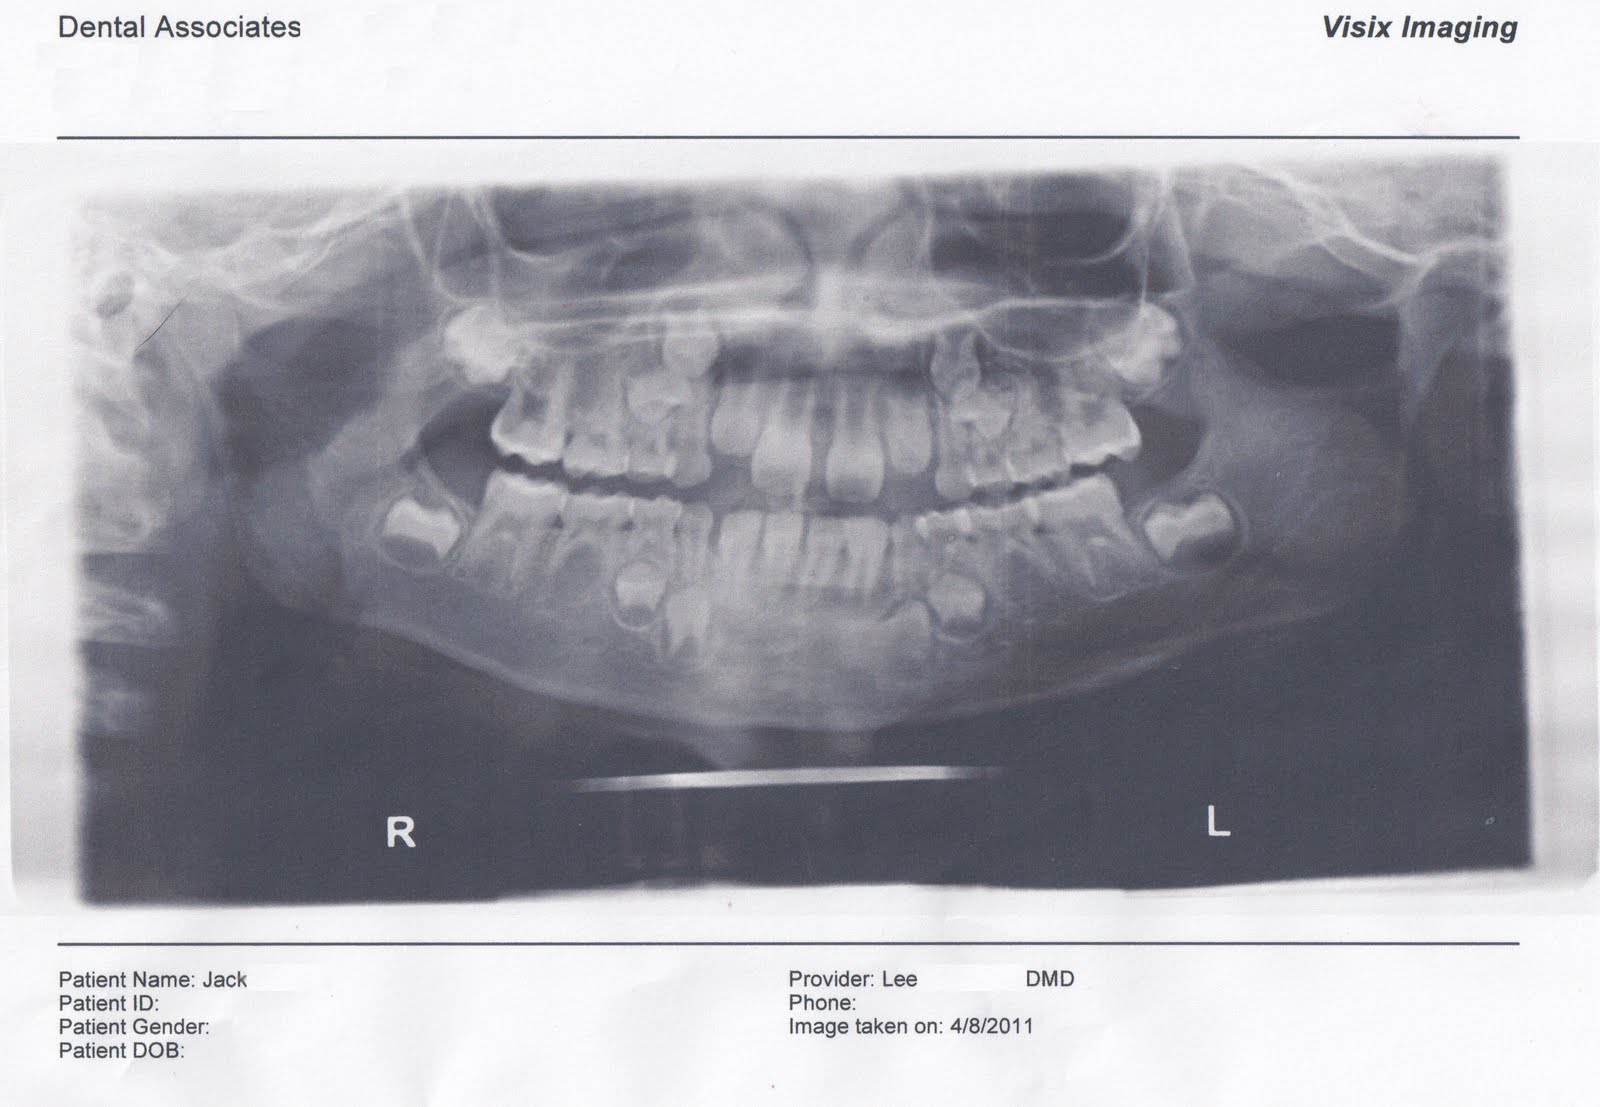

Dental Xrays Why, Which, & When? Digital Xrays Charlotte dentist Dental X-Rays Linked To Brain Tumors This study evaluates the risk of benign brain tumors (bbts) and malignant brain tumors (mbts) associated with. A control group of 1350 individuals was frequency matched on age, sex, and geography (controls). Ionizing radiation is a consistently identified and potentially modifiable risk factor for meningioma, the most frequently. Dental X-Rays Linked To Brain Tumors.

Dental xrays Do xrays show tumors? IFHNOS Auckland 2016 Dental X-Rays Linked To Brain Tumors This study evaluates the risk of benign brain tumors (bbts) and malignant brain tumors (mbts) associated with. A control group of 1350 individuals was frequency matched on age, sex, and geography (controls). Ionizing radiation is a consistently identified and potentially modifiable risk factor for meningioma, the most frequently. Dental X-Rays Linked To Brain Tumors.